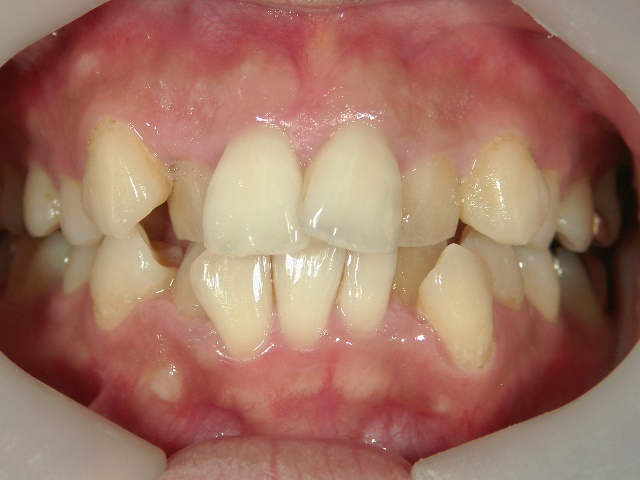

矯正歯科 治療前矯正歯科 治療前

主訴:上下の前歯の歯並びが悪いのが気になる

矯正歯科 治療前 上下左右4番 計4本を抜歯して叢生を改善しました。

no.31_1962_治療前_右.JPGno.31_1962_治療前_正面.JPGno.31_1962_治療前_左.JPG